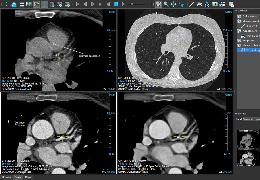

ANYTHINK 经导管主动脉瓣膜置换术分析系统